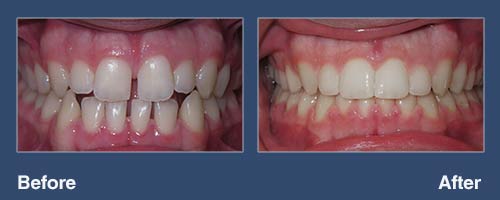

Crowding of the teeth

Patient started orthodontic treatment at age fourteen and wore traditional braces for 24 months. He loves his new smile!